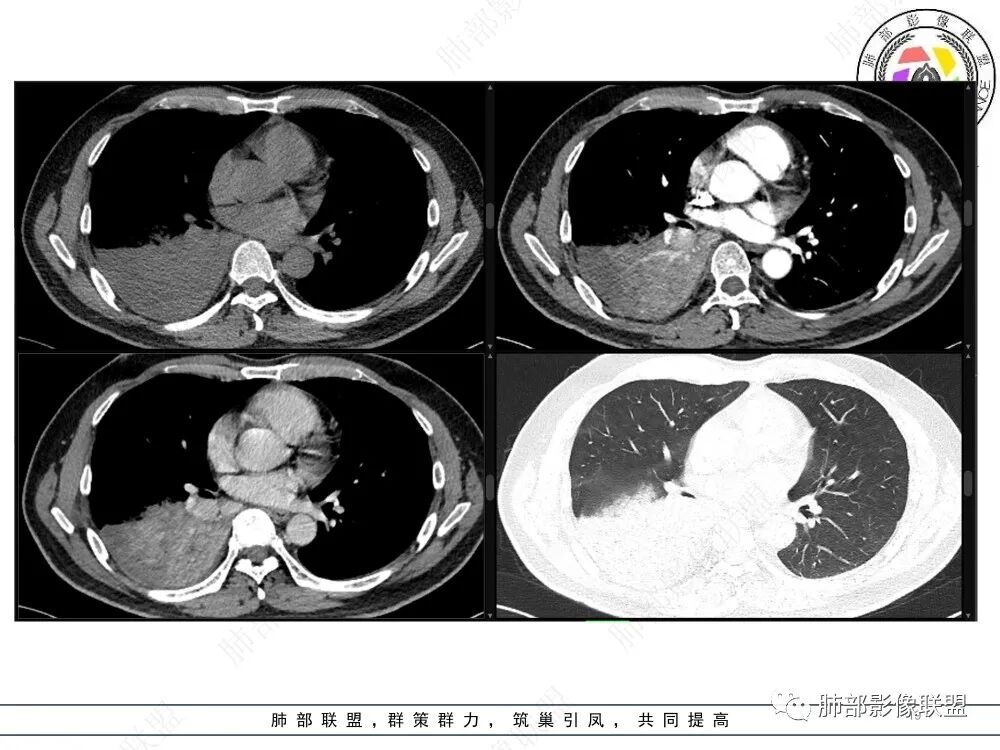

中央型肿瘤pk周围型肿瘤  。壮年男性,热咳一周伴气喘,中性白细胞升高,临床是个感染过程。支持中央型病变的证据:1  肺门明显强化结节 2 横s征  3 支气管粘液栓  4 主支气管变窄,似见冰山征      支持周围型病变:1 按叶段塑形  2 血管造影征  3 病灶内弥漫高强化  4 周围伴磨玻璃灶,但境界不清继发感染?误吸?综合 中央型肿瘤可能大:类癌》鳞癌

首先血管未见明显侵犯、移位,提示病灶:炎性;肿瘤:外朝内——含粘液类腺癌(肺门淋巴结转移),腔内肿瘤(鳞癌、腺癌、类癌、小细胞、粘液表皮等)

从强化看:外周密度低,强化弱

就不太符合腔内肿瘤远端不张的表现,因为外围不张——强化明显

这一例反了

按这个特点周围要考虑肿瘤组织

CT提示1、右肺下叶气管堵塞伴阻塞性肺不张,肺炎征象。2、破坏气管周边肿物可见结节样,肿物整体呈团块样

3、增强可见肿物明显强化。4、肿瘤内部血管可见破坏征象,但是破坏不完全。5.肿物坏死征象不明显。

实变强化考虑全部都是肿瘤浸润

冠状位重建有钻缝的感觉